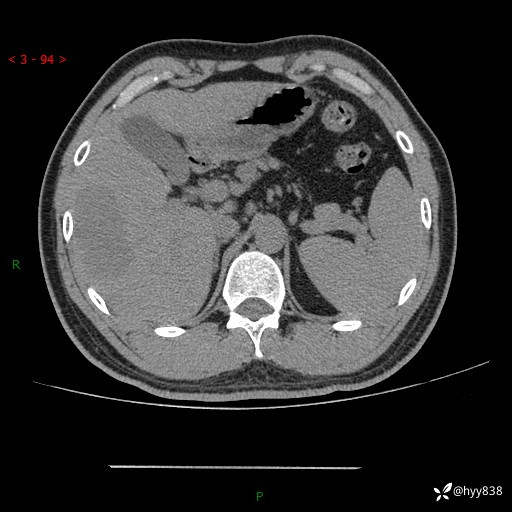

静脉期

img